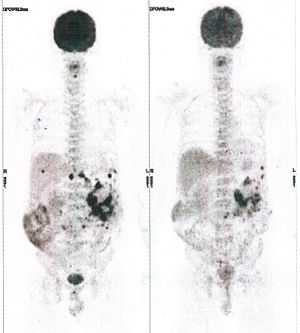

CASE NO: 3 (PROSTATE CANCER)

A middle-aged man with castration resistant prostate cancer, having failed all currently available cancer treatment, was very weak, and getting worse every day. The PET/CT scan showed he had massive bone metastases. After a few treatment, all the bone metastases went into remission. About 6 months later, he is still in remission.

CASE NO: 4 (PROSTATE CANCER)

A middle-aged man with castration resistant prostate cancer and massive bone metastases, failed all currently available cancer treatment, including with the new and expensive drug XTANDI. After a few treatment, most of the bone metastases went into remission, and the remaining ones are less active. Treatment will continue. Cases no: 3 and 4 show that terminal prostate cancer today can be cured with our new cancer treatment.